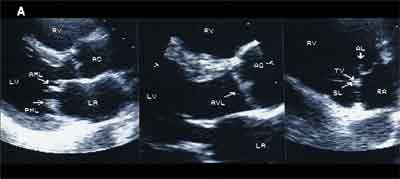

An echocardiographic study showed abnormally thickened and rigid mitral, aortic, and deformed tricuspid leaflets (A). Color flow Doppler images showed abnormal regurgitation at all 3 valves without stenosis (B). Peak right ventricular pressure was 26 mm Hg. Left ventricular function was normal (estimated ejection fraction of 60% to 65%). Because no previous echocardiogram—obtained before the patient started taking the drugs—was available, images of normal cardiac valves are shown for comparison (C).